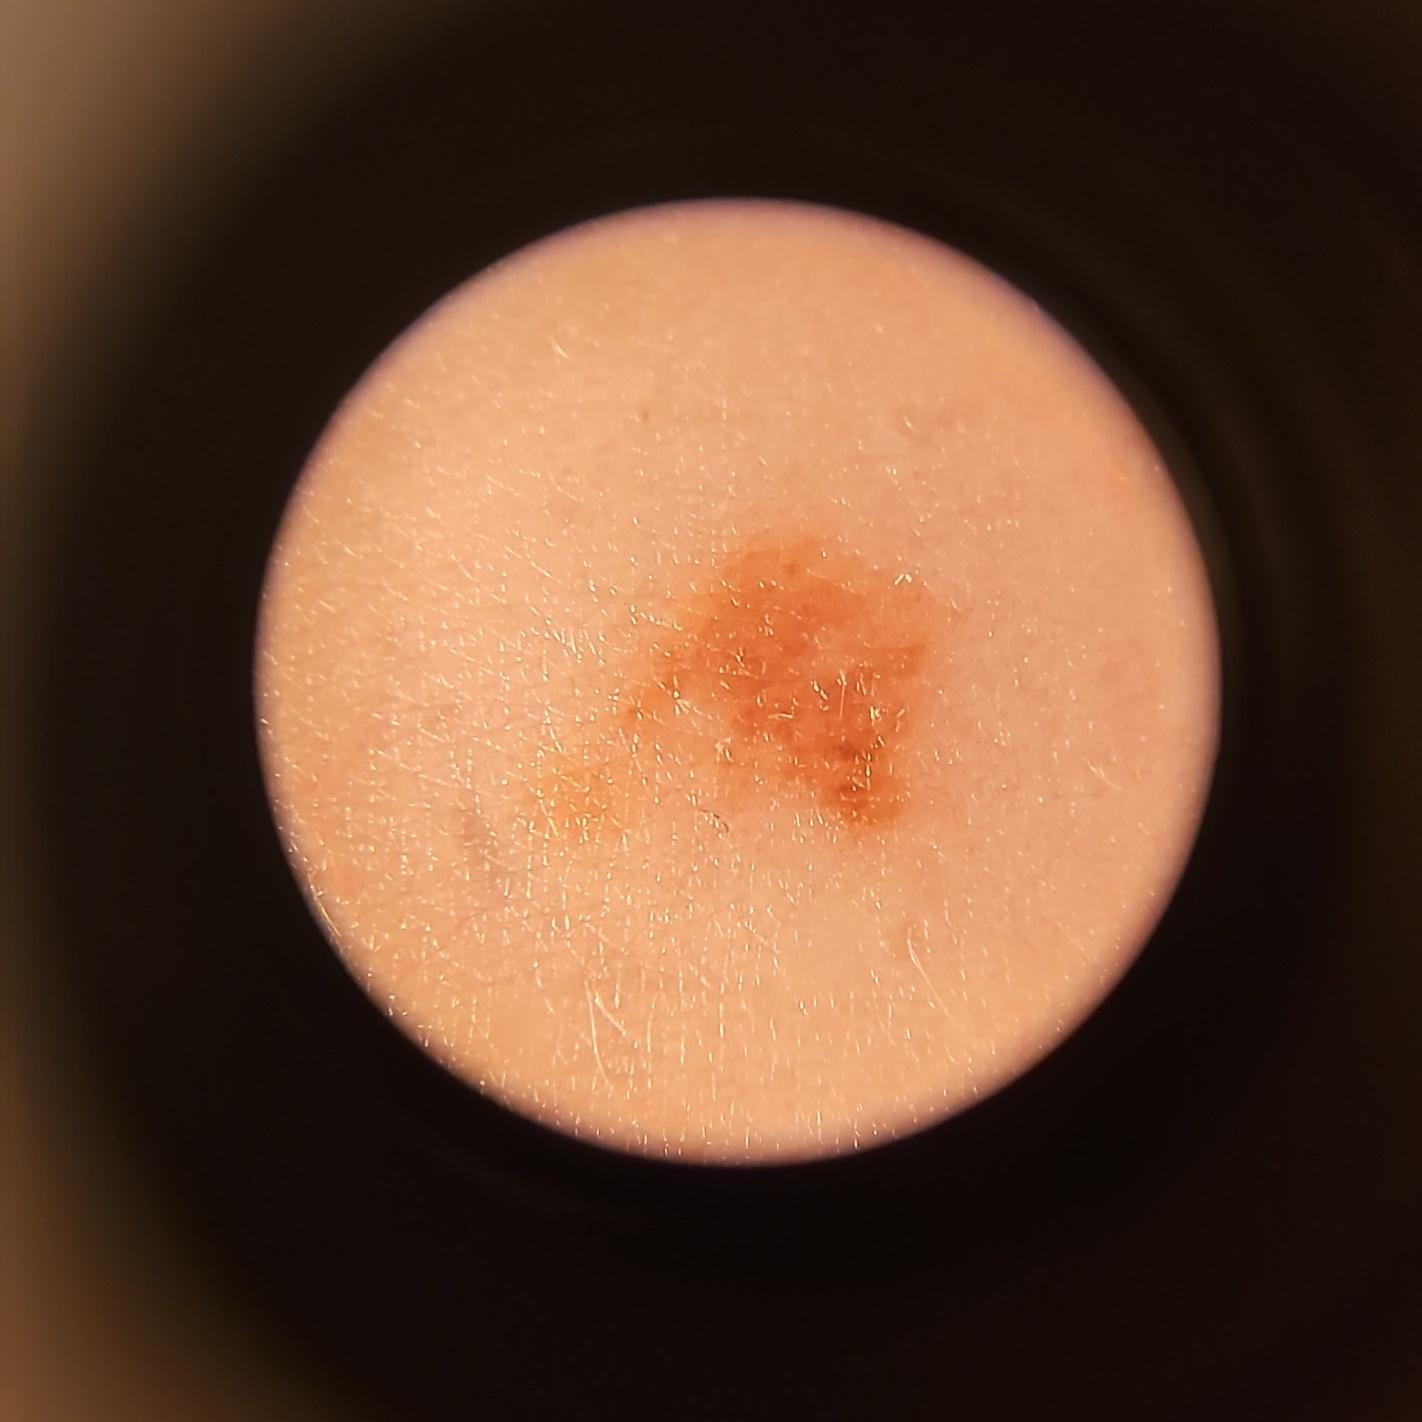

ISIC_0151728

acquisition_day 0

age_approx 45

anatom_site_1 Trunk

anatom_site_2 Anterior trunk

anatom_site_general anterior torso

diagnosis_1 Benign

image_type dermoscopic

personal_hx_mm True

sex female